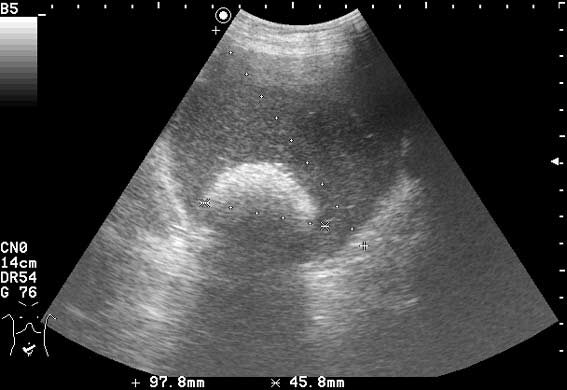

УЗИ: дермоидная киста яичника

Женщина средних лет, лечилась в гастро- отделении, скрининговый осмотр низа живота.

Это - дермоид яичника.

Больная оперирована в гинекологическом отделении.